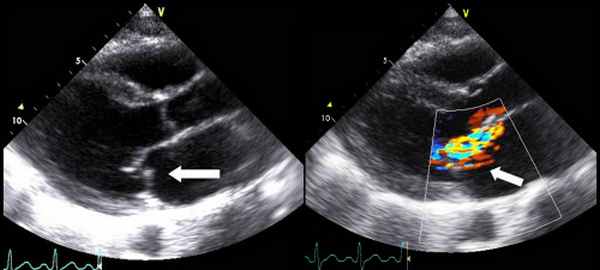

Причиной стеноза митрального клапана обычно является ревматизм. Редко стеноз МК может быть врожденным, связанным с дегенеративной кальцификацией, гиперэозипофилией, инфекционным эндокардитом, влиянием радиации и лекарственных препаратов. Типичные признаки ревматического стеноза МК можно обнаружить при ЭхоКГ в М- и В-режимах. Площадь отверстия МК измеряют планиметрически в парастернальной позиции по короткой оси. Трехмерная ЭхоКГ позволяет лучше определить площадь отверстия клапана у больных со стенозом МК или у перенесших комиссуротомию.

У многих больных эффективным методом лечения стеноза МК является митральная баллонная вальвулопластика. Для прогноза результатов этой процедуры используют ЭхоКГ-индекс, который рассчитывают на основании толщины, кальцификации, подвижности створок и утолщения подклепанных структур. Пациенты с ЭхоКГ-индексом 8. Спаяние створок по комиссурам или кальцификации комиссур служат дополнительными важными признаками для прогноза после чрескожной вальвулопластики или вальвулотомии.

ЧПЭхоКГ используют у больных со стенозом МК главным образом для исключения тромбоза ЛП или его ушка после громбоэмболических эпизодов или перед митральной баллонной вальвулопластикой. Иногда ЧПЭхоКГ или внутрисердечную ЭхоКГ выполняют во время баллонной вальвулопластики для пункции перегородки или выбора местоположения баллона.